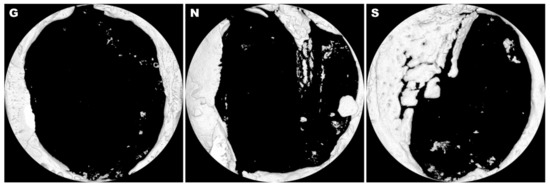

3.2. Histological Analysis

| New Bone formation (%) | 1.24 ± 1.10 | 1.26 ± 1.05 | 8.26 ± 5.43 * |